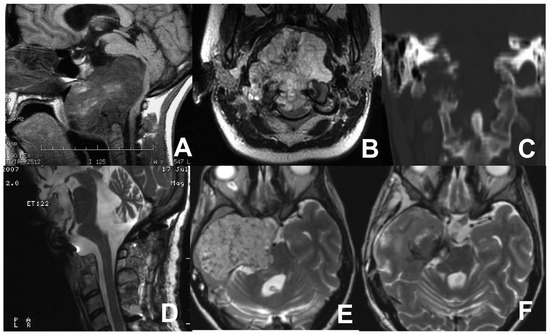

3.4. Third Case: Two-Staged Transoral Approach and Posterior Midline Occipitocervical Fusion—Subtemporal/Infratemporal and Retrosigmoid Approaches for Tumor Relapse